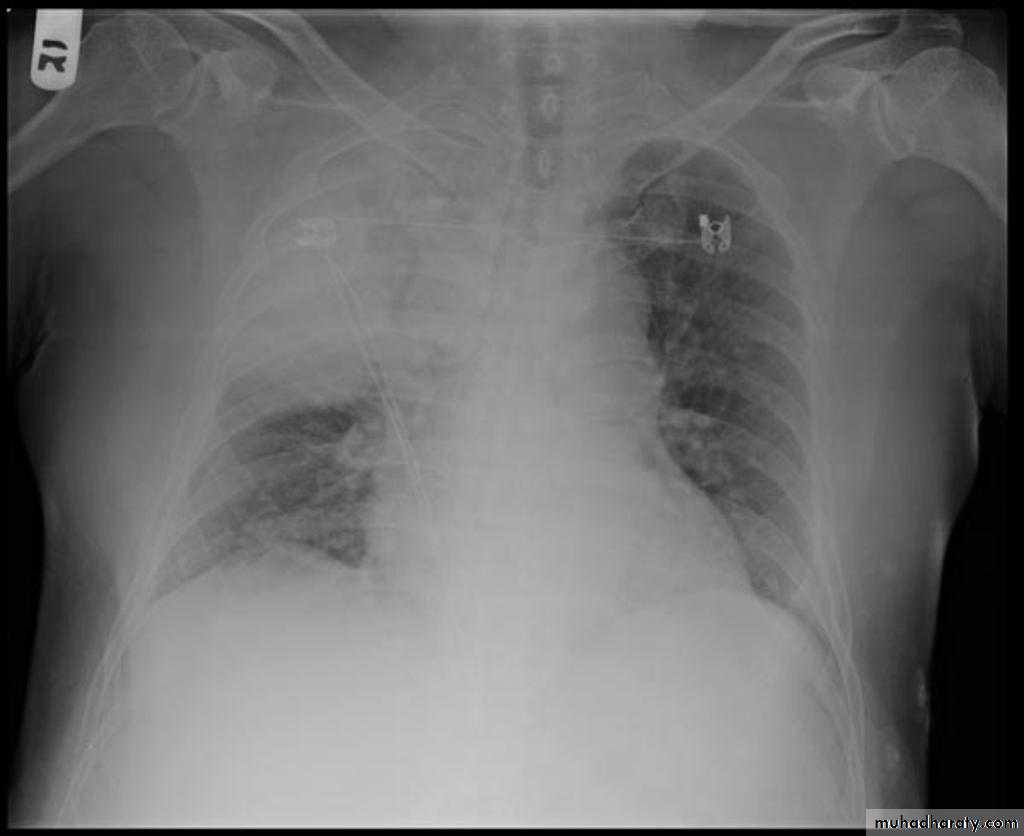

Homogenus opacity of the left hemithorax with shifting of the trachea to the same sidePleural effusion

Homogenus opacity of right lower zone with meniscus signOblitration of right cardiophrenic and costophrenic angles

Homogenus opacity of the right hemithorax

Oblitration of cardiophrenic and costophrenic angles

Shifting of the trachea to the opposite side

Pleural effusion

Homogenus opacity of right lower lobe with Oblitration of right cardiophrenic and costophrenic angles.

Meniscus sign